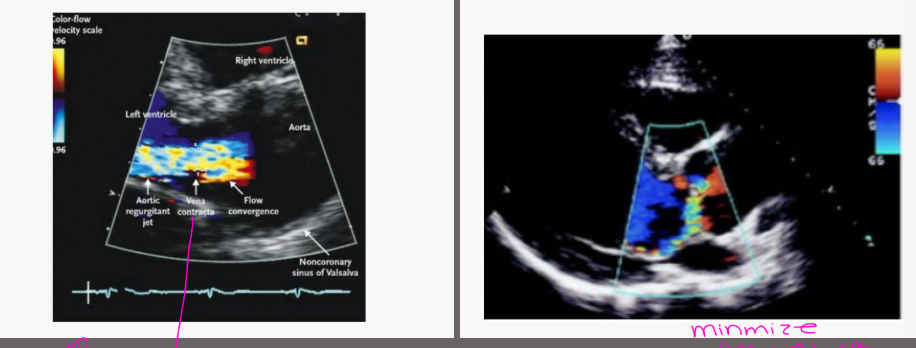

Assessment begins in what view

Color doppler shows the presence of what

measure what

Assessment begins in PLAX

Color Doppler shows the presence of

aortic regurgitation

Measure the LVEDD for LV dilatation

Aorta measurements including Sinus of

Valsalva, ST junction, and proximal aorta

Valve etiology

what is this showing

which one is central VS eccentric AR

Central is the 1st pic

eccentric is the 2nd pic

AR via color flow may be unreliable due to what

Unreliable due to

diastolic blood pressure

and acute AR